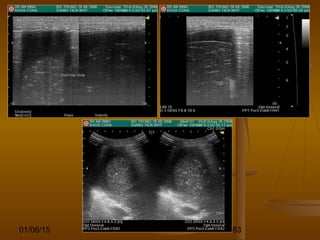

DẤU HIỆU BIA BẮNDẤU HIỆU BIA BẮN

(TARGET SIGN)(TARGET SIGN)

 Hình ảnh những vòng đồng tâm hồi âm dày và hồiHình ảnh những vòng đồng tâm hồi âm dày và hồi

âm kém xen kẽ hoặc là vòng tròn hồi âm kém vớiâm kém xen kẽ hoặc là vòng tròn hồi âm kém với

trung tâm hồi âm dày.trung tâm hồi âm dày.

 Dấu hiệu này có thể thấy ở nhiều bệnh lý của ốngDấu hiệu này có thể thấy ở nhiều bệnh lý của ống

tiêu hóa.tiêu hóa.

 Nó có thể là sự dày lên của vách ống tiêu hóa doNó có thể là sự dày lên của vách ống tiêu hóa do

viêm (VRT, viêm ĐT giả mạc), u, thiếu máu, phìviêm (VRT, viêm ĐT giả mạc), u, thiếu máu, phì

đại (hẹp môn vị phì đại).đại (hẹp môn vị phì đại).

 Hoặc có thể là hình ảnh của các đoạn ống tiêuHoặc có thể là hình ảnh của các đoạn ống tiêu

hóa lồng vào nhau (lồng ruột).hóa lồng vào nhau (lồng ruột).

Viêm ruột thừa cấp